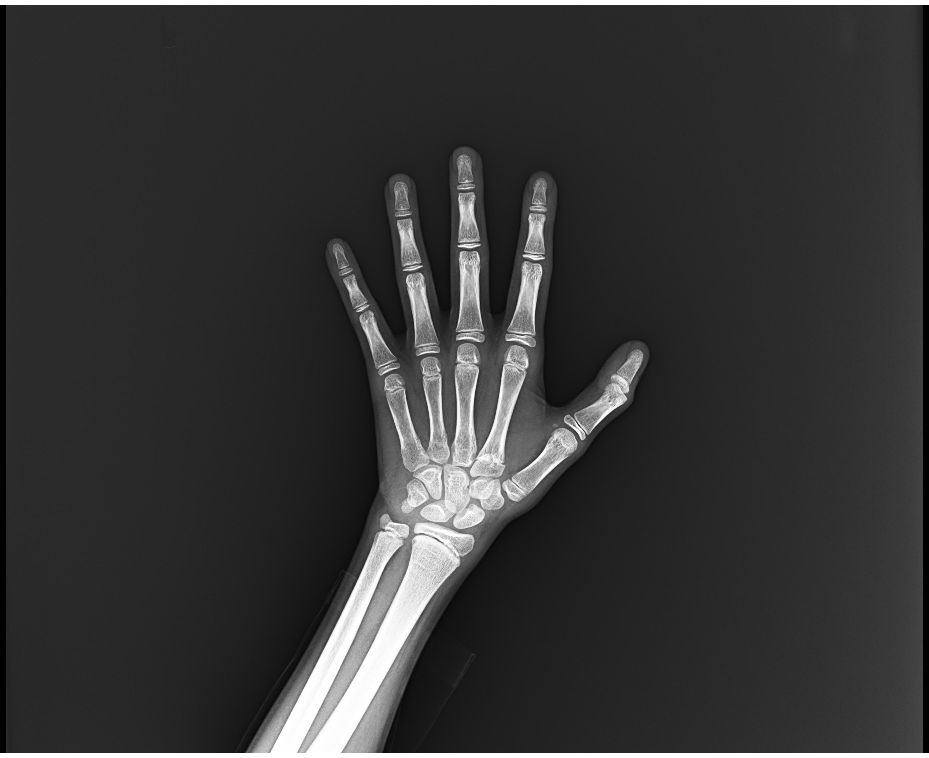

兒童骨齡評估

透過左手X光片判讀骨骼成熟度,預測成年身高,掌握黃金生長發育期。

性早熟生長遲緩想了解身高潛力的兒童

同樣地,兒童的生長發育只有一次。透過骨齡檢測,我們能客觀判斷孩子的生長潛力。無論是性早熟的治療或生長遲緩的介入,都需要精準的醫療判斷,而非盲目補充營養品。